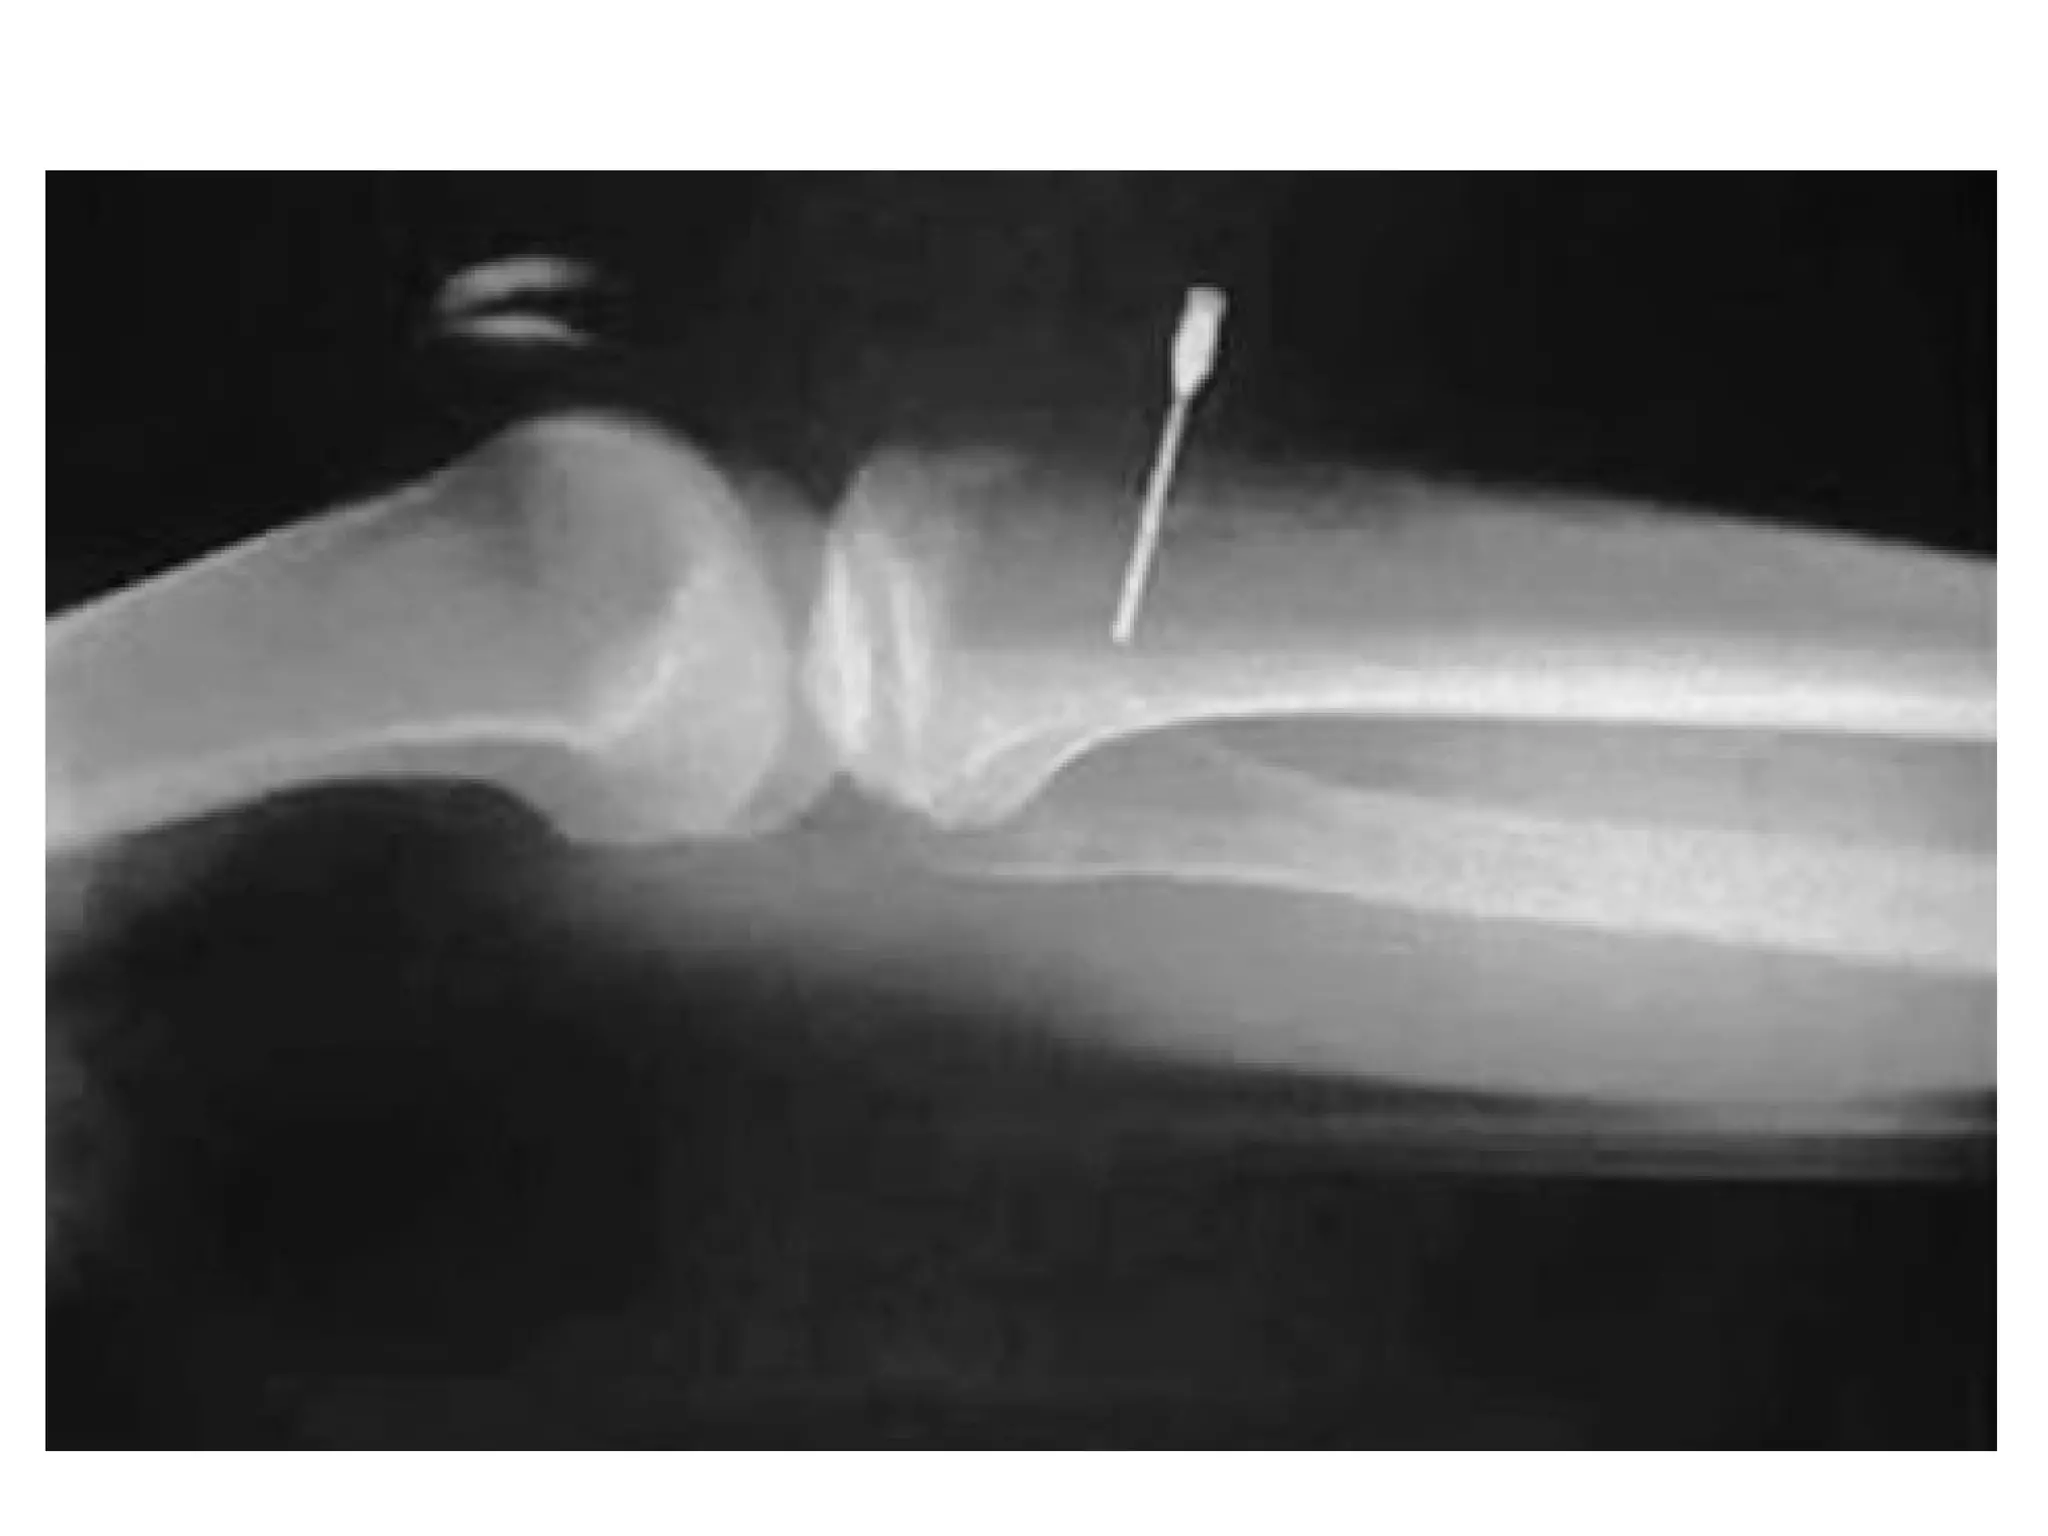

• Extremities – examine for swelling, deformity,

tenderness, crepitus. Note neurovascular status.

Obviously deformed limbs should be reduced and

immobilized using cast or traction for example